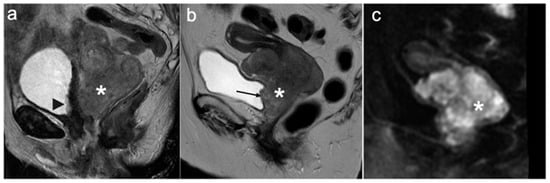

9. Recurrent Cervical Cancer